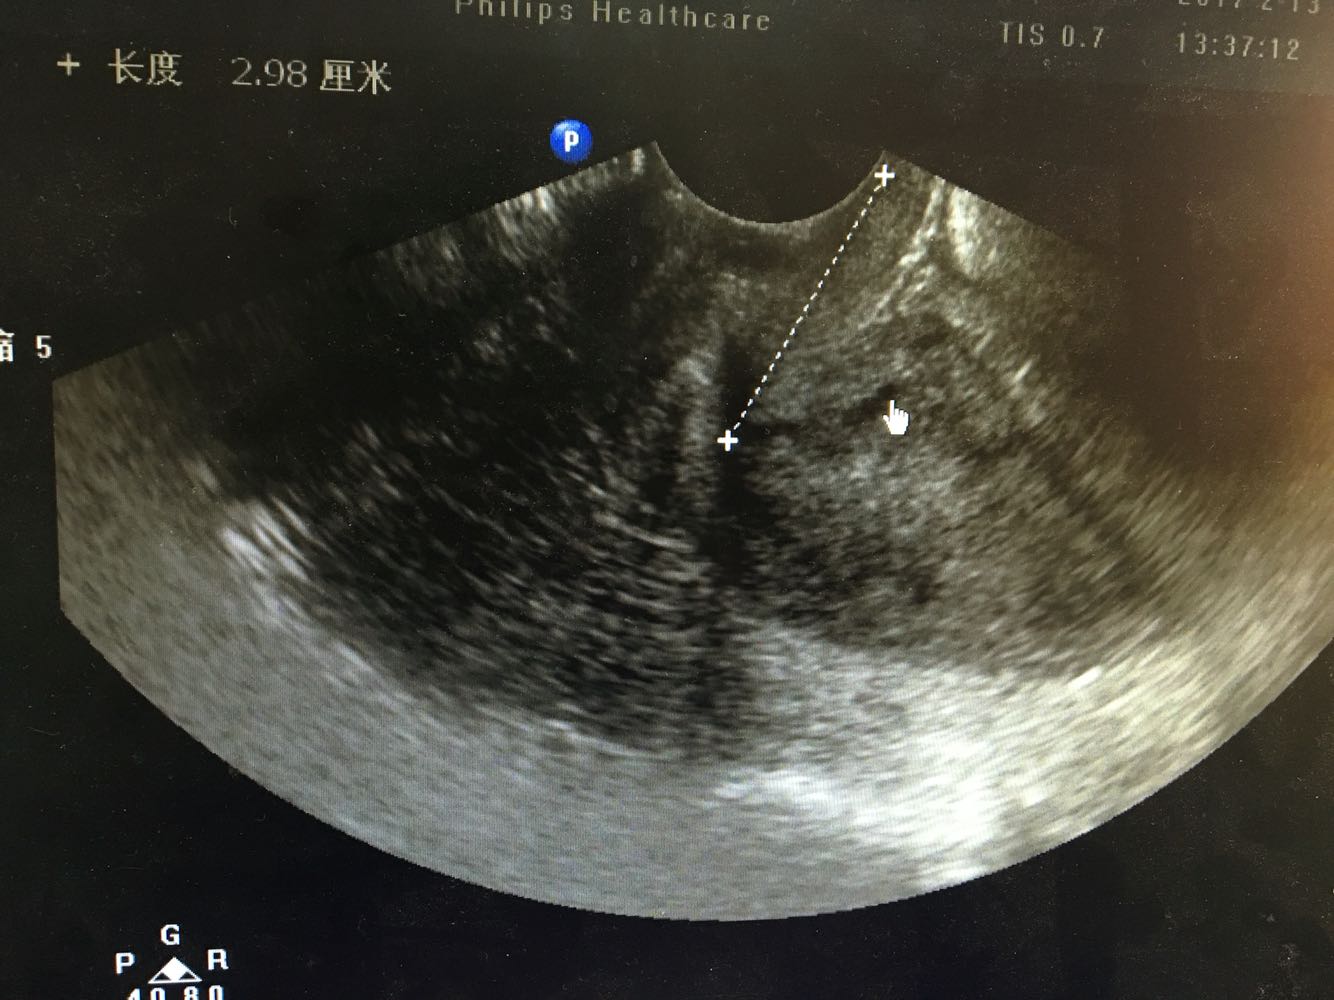

妇科检查:  妇科检查: 外阴(-);阴道畅,少量血性分泌物;宫颈轻糜,无活动性出血;宫体中位,常大,质中,无压痛;附件未及异常,无压痛。 辅助检查:我院 【ECG】ST段改变。    【妇科B超】内膜双侧厚:16,回声不均匀,内引出血流信号,与周围肌层分界不清。诊断意见:子宫内膜增厚,回声不均匀,Ca待查,请结合临床。

诊断:绝经后出血 诊疗方案:患者入院后完善各项检查排除手术禁忌症,行B超下分段诊刮术,刮勺搔刮宫颈管极少量组织刮出,并涂片送检脱落细胞。 探宫腔深6.5cm,刮勺搔刮宫腔四周2圈,感宫壁滑腻,刮出少量鱼肉样组织,送病理, 同时涂片送检脱落细胞 ,手术顺利。